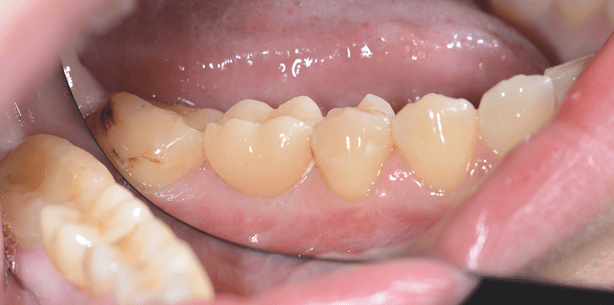

Auf eine postoperative Versorgung mit einer provisorischen Kappe wurde im vorliegenden Fall verzichtet (Abb. 19). Nach der Abdrucknahme wurde nur das Emergenzprofil mit der im wissenschaftlichen Prelaunch verfügbaren Schutzkappe gesichert. Im zahntechnischen Labor wurde anschließend die vollkeramische, monolithische Einzelzahnrestauration hergestellt (Abb. 20). Zur Herstellung des Meistermodells wählte das Dentallabor das passende konfektionierte Manipulierimplantat aus; insofern folgte die weitere prothetische Vorgehensweise den erprobten, zahntechnischen Herstellungsprotokollen. Bei der Kontrolle der implantatprothetischen Restauration 14 Tage nach Eingliederung zeigte sich klinisch eine gute biologisch-funktionelle und ästhetische Integration der metallfreien Restauration (Abb. 21). Insbesondere imponierte die sehr gute und vollkommen reizlose Anlagerung der periimplantären Weichgewebe.